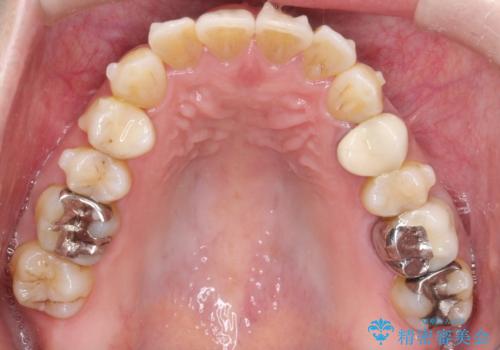

- 前歯のがたつきを主訴に来院されました。

なるべく目立たない矯正をご希望されたので、インビザラインにて治療することとなりました。